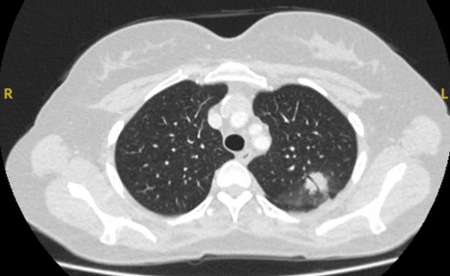

Cortes de tomografia computadorizada (TC) de dois casos com nódulos perifissurais benignos. Observe as margens lisas e a fissura adjacente normal e intacta

Do acervo de Dr. George Tsaknis, MD, PhD, FRCP (Londres), MRQA, MAcadMEd, PGCert; usado com permissão